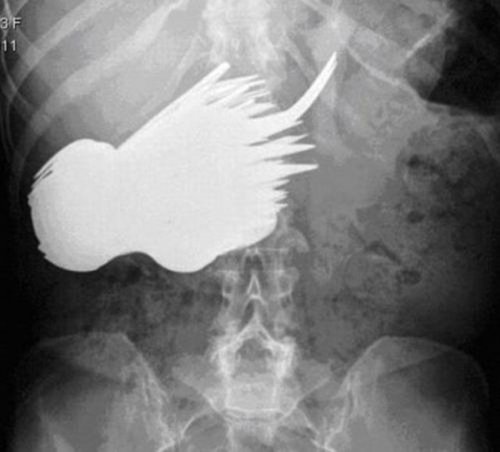

52-летняя женщина из Нидерландов по имени Маргарет Даалман (Margaret Daalman) обратилась в больницу с жалобой на боль в желудке и один взгляд, брошенный на снимок, объясняет причину дискомфорта. Хирурги из Роттердама были поражены снимками, на которых в её желудке обнаружилось 78 различных столовых приборов. ![]()